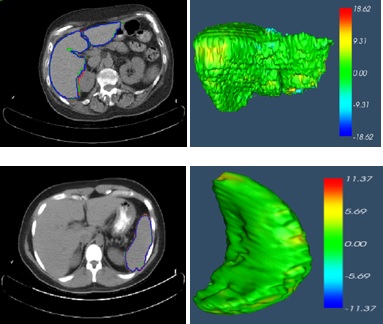

| The 3D Shape Constrained GC |

| ★Method 3 — 3D Shape Constrained Graph Cut |

| The executable version of 3D shape constrained GC with user interface can be downloaded (please read the instructions from http://www.mipg.upenn.edu/~cavass/ before downloading. This is a zip file, delete extention “.odt” after downloading. ). GC user interface with CAVASS, more infomation about cavass can be found from official website: http://www.mipg.upenn.edu/~cavass/ |